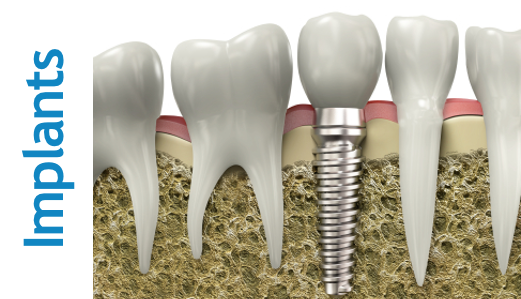

THE BEST IMPLANT IS THE ONE PLACED PERFECTLY!

There are about 150 different producers of dental implants. Luckily, most of them do their job well and the best ones create implants with the precision required like in airplane engine construction. Some implants are more durable than others over the years, the difference lies in their ability to sustain high bone coefficient. However, the success of the whole implant treatment depends not on an implant per se but on its perfect placement and fixing. -